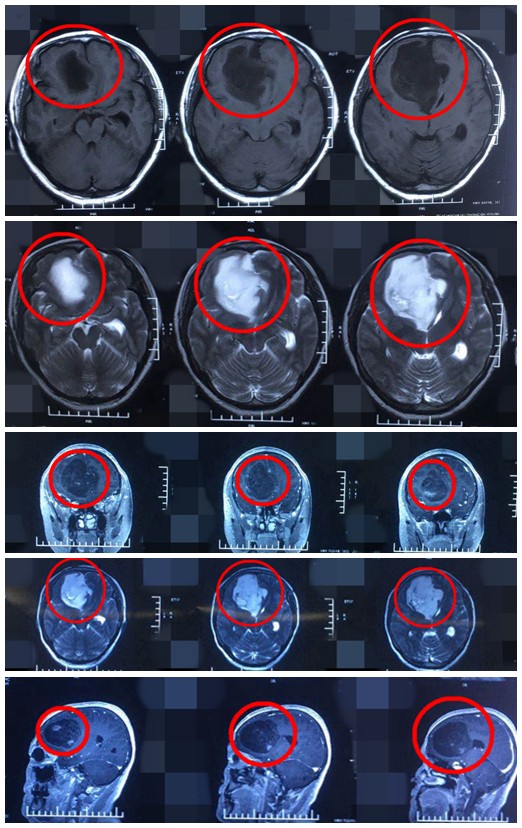

影像资料

唐都医院神经外科五病区贾栋主任根据曹屹东教授的病例报告制定手术方案,并指出应该尽可能全切肿瘤,解决患者问题。

手术由贾栋主任主刀,显微镜下显示肿瘤边界比较清楚,全切了肿瘤。